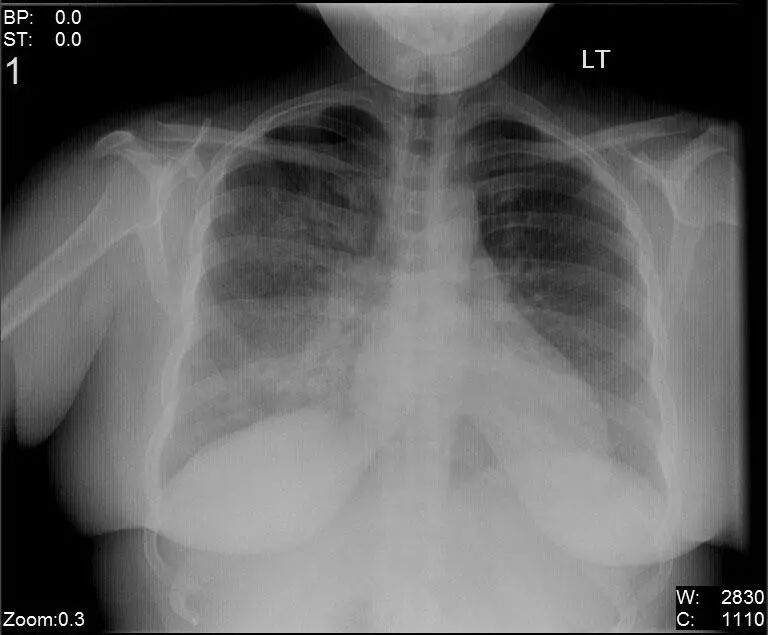

图1.1 细菌性肺炎。右上叶肺炎患者的放射影像。胸廓前后径增大,提示有慢性阻塞性肺疾病(COPD)。